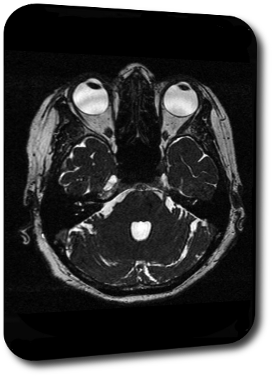

Kopfschmerz

Prof. Dr. Christian Geis

Universitätsklinikum Jena